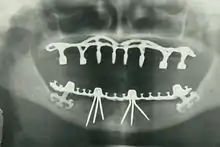

مدة دراسة طب الأسنان عادة لا تقل عن 4 سنوات وتختلف المدة حسب الدولة والنظام التعليمي، مثلا يجتاز جميع أطباء الأسنان في الولايات المتحدة الأمريكية ثلاث سنوات على الأقل من الدراسة الجامعية وتقريبا ما ينجح جميعهم بنيل شهادة البكلوريوس. هذا التحصيل العلمي يتبع بأربع سنوات دراسية في كلية طب الأسنان لتأهيله كطبيب في جراحة الأسنان "Doctor of Dental Surgery" (DDS) أو طبيب في طب الأسنان "Doctor of Dental Medicine" (DMD). أما في الجامعات المصرية، مدة الدراسة تكون عبارة عن 5 سنوات، بالإضافة الي سنة سادسة وهي سنة الأمتياز حيث يقوم الطبيب بالمرور علي جميع أقسام طب الأسنان لممارسة أكبر عدد من الحالات.[6] يمكنهم بالاعتماد على طبيعة تدريبهم العام إنجاز معظم المعالجات السنية كالمعالجات الترميمية ( الترميمات والتيجان والجسور ) المعالجات التعويضية ( الأجهزة المتحركة ) والمعالجات اللبية و معالجات النسج الداعمة ( اللثة ) وخلع الأسنان وإجراء الفحوصات والصور الشعاعية ( x-rays ) والتشخيص. يمكن لأطباء الأسنان أيضاً وصف أدوية كالمضادات الحيوية أو المسكنات أو أي أدوية أخرى تستخدم في تدبير المريض.

- طب الأسنان التعويضي التعويضات السنية : وتشمل الجسور الثابتة والزرعات والتعويض فوق الزرعات والأجهزة السنية الطقوم المتحركة الكاملة أو الجزئية